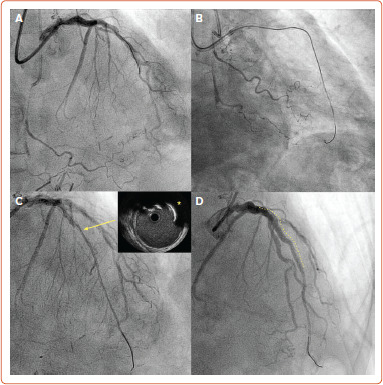

Despite early stagnation in success rates for percutaneous coronary intervention for chronic total occlusion with the traditional antegrade wiring approach, the introduction of dissection/re-entry techniques and the retrograde approach opened new avenues for operators to tackle more complex occlusions. Dissection/re-entry techniques (both antegrade and retrograde) are commonly used in angiographic scenarios characterised by long, tortuous and calcified occlusions, as well as in those with proximal cap ambiguity. Familiarity and comfort using the extraplaque space (with either an antegrade or retrograde approach) have become fundamental to achieving safe and effective recanalisation of complex chronic total occlusions. This review provides an overview of different contemporary antegrade and retrograde dissection re-entry techniques and their acute and longer-term outcomes.